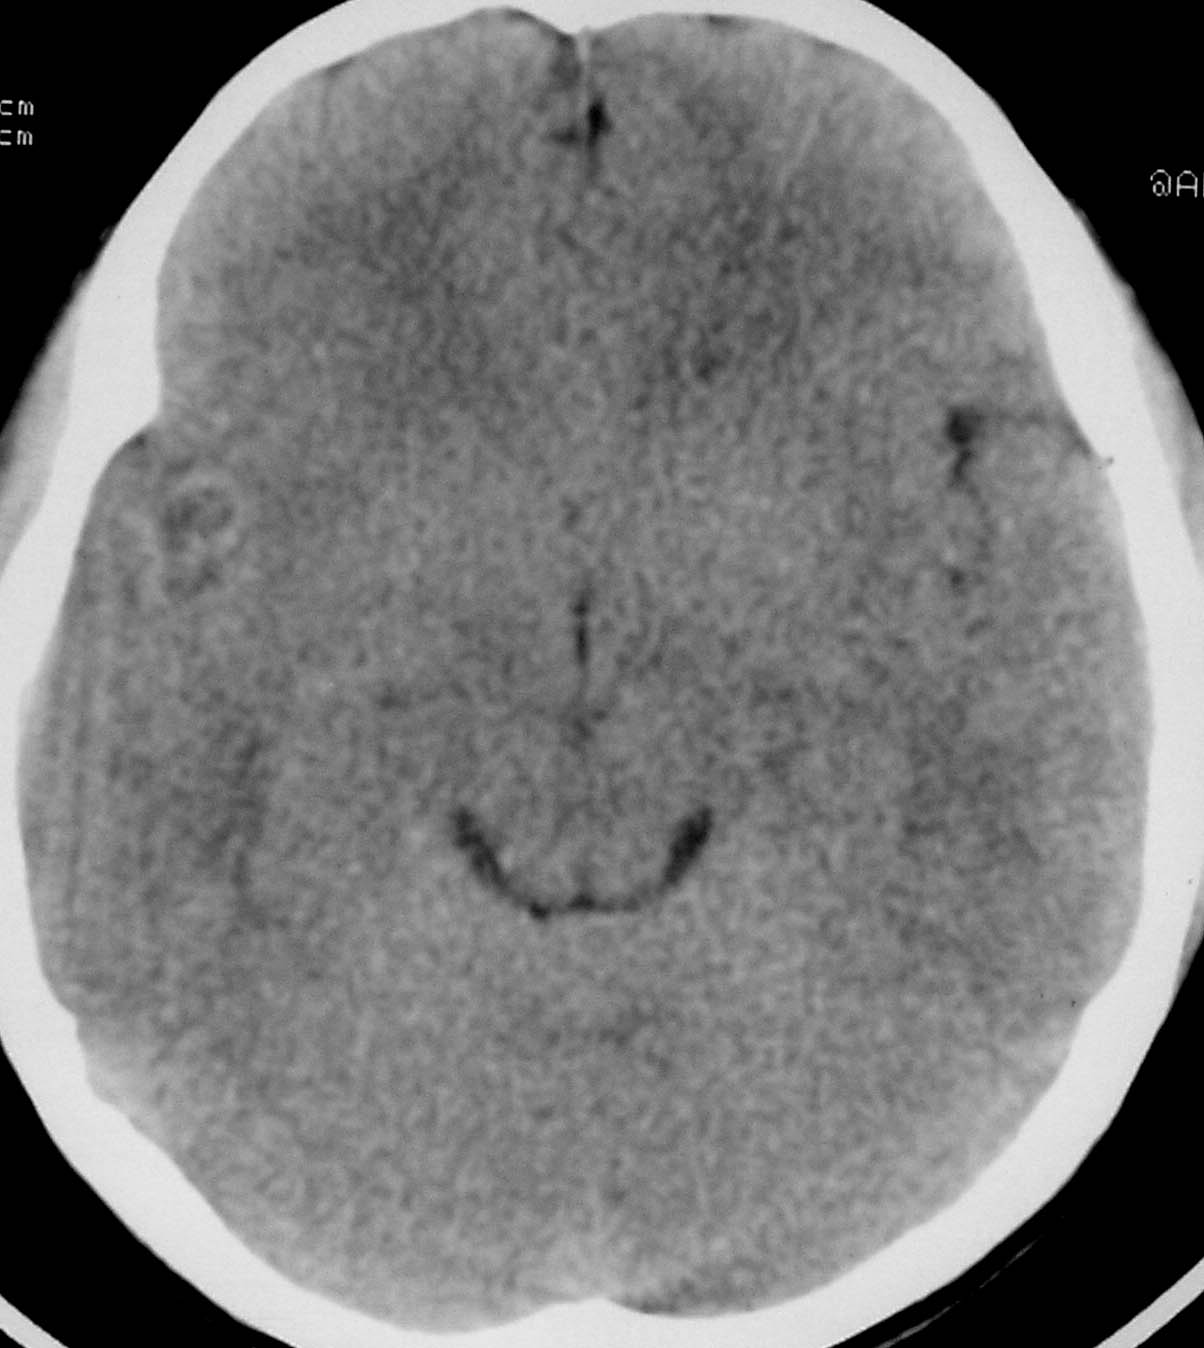

以下是引用余辉在2007-4-28 19:55:00的发言:[br]血管畸形?增强一下

以下是引用jw-830在2007-4-28 20:22:00的发言:[br]考虑血管畸形可能建议增强

以下是引用ysxyy在2007-4-29 21:14:00的发言:[br]像是假像,如果不放心可以偿试一下:[br]你用听眦线为基线扫一下,再用听眶线扫一下,就是说用不同的角度扫同一个地方;[br]看看有无变化,是不是有相同或相似的表现,即可鉴别;